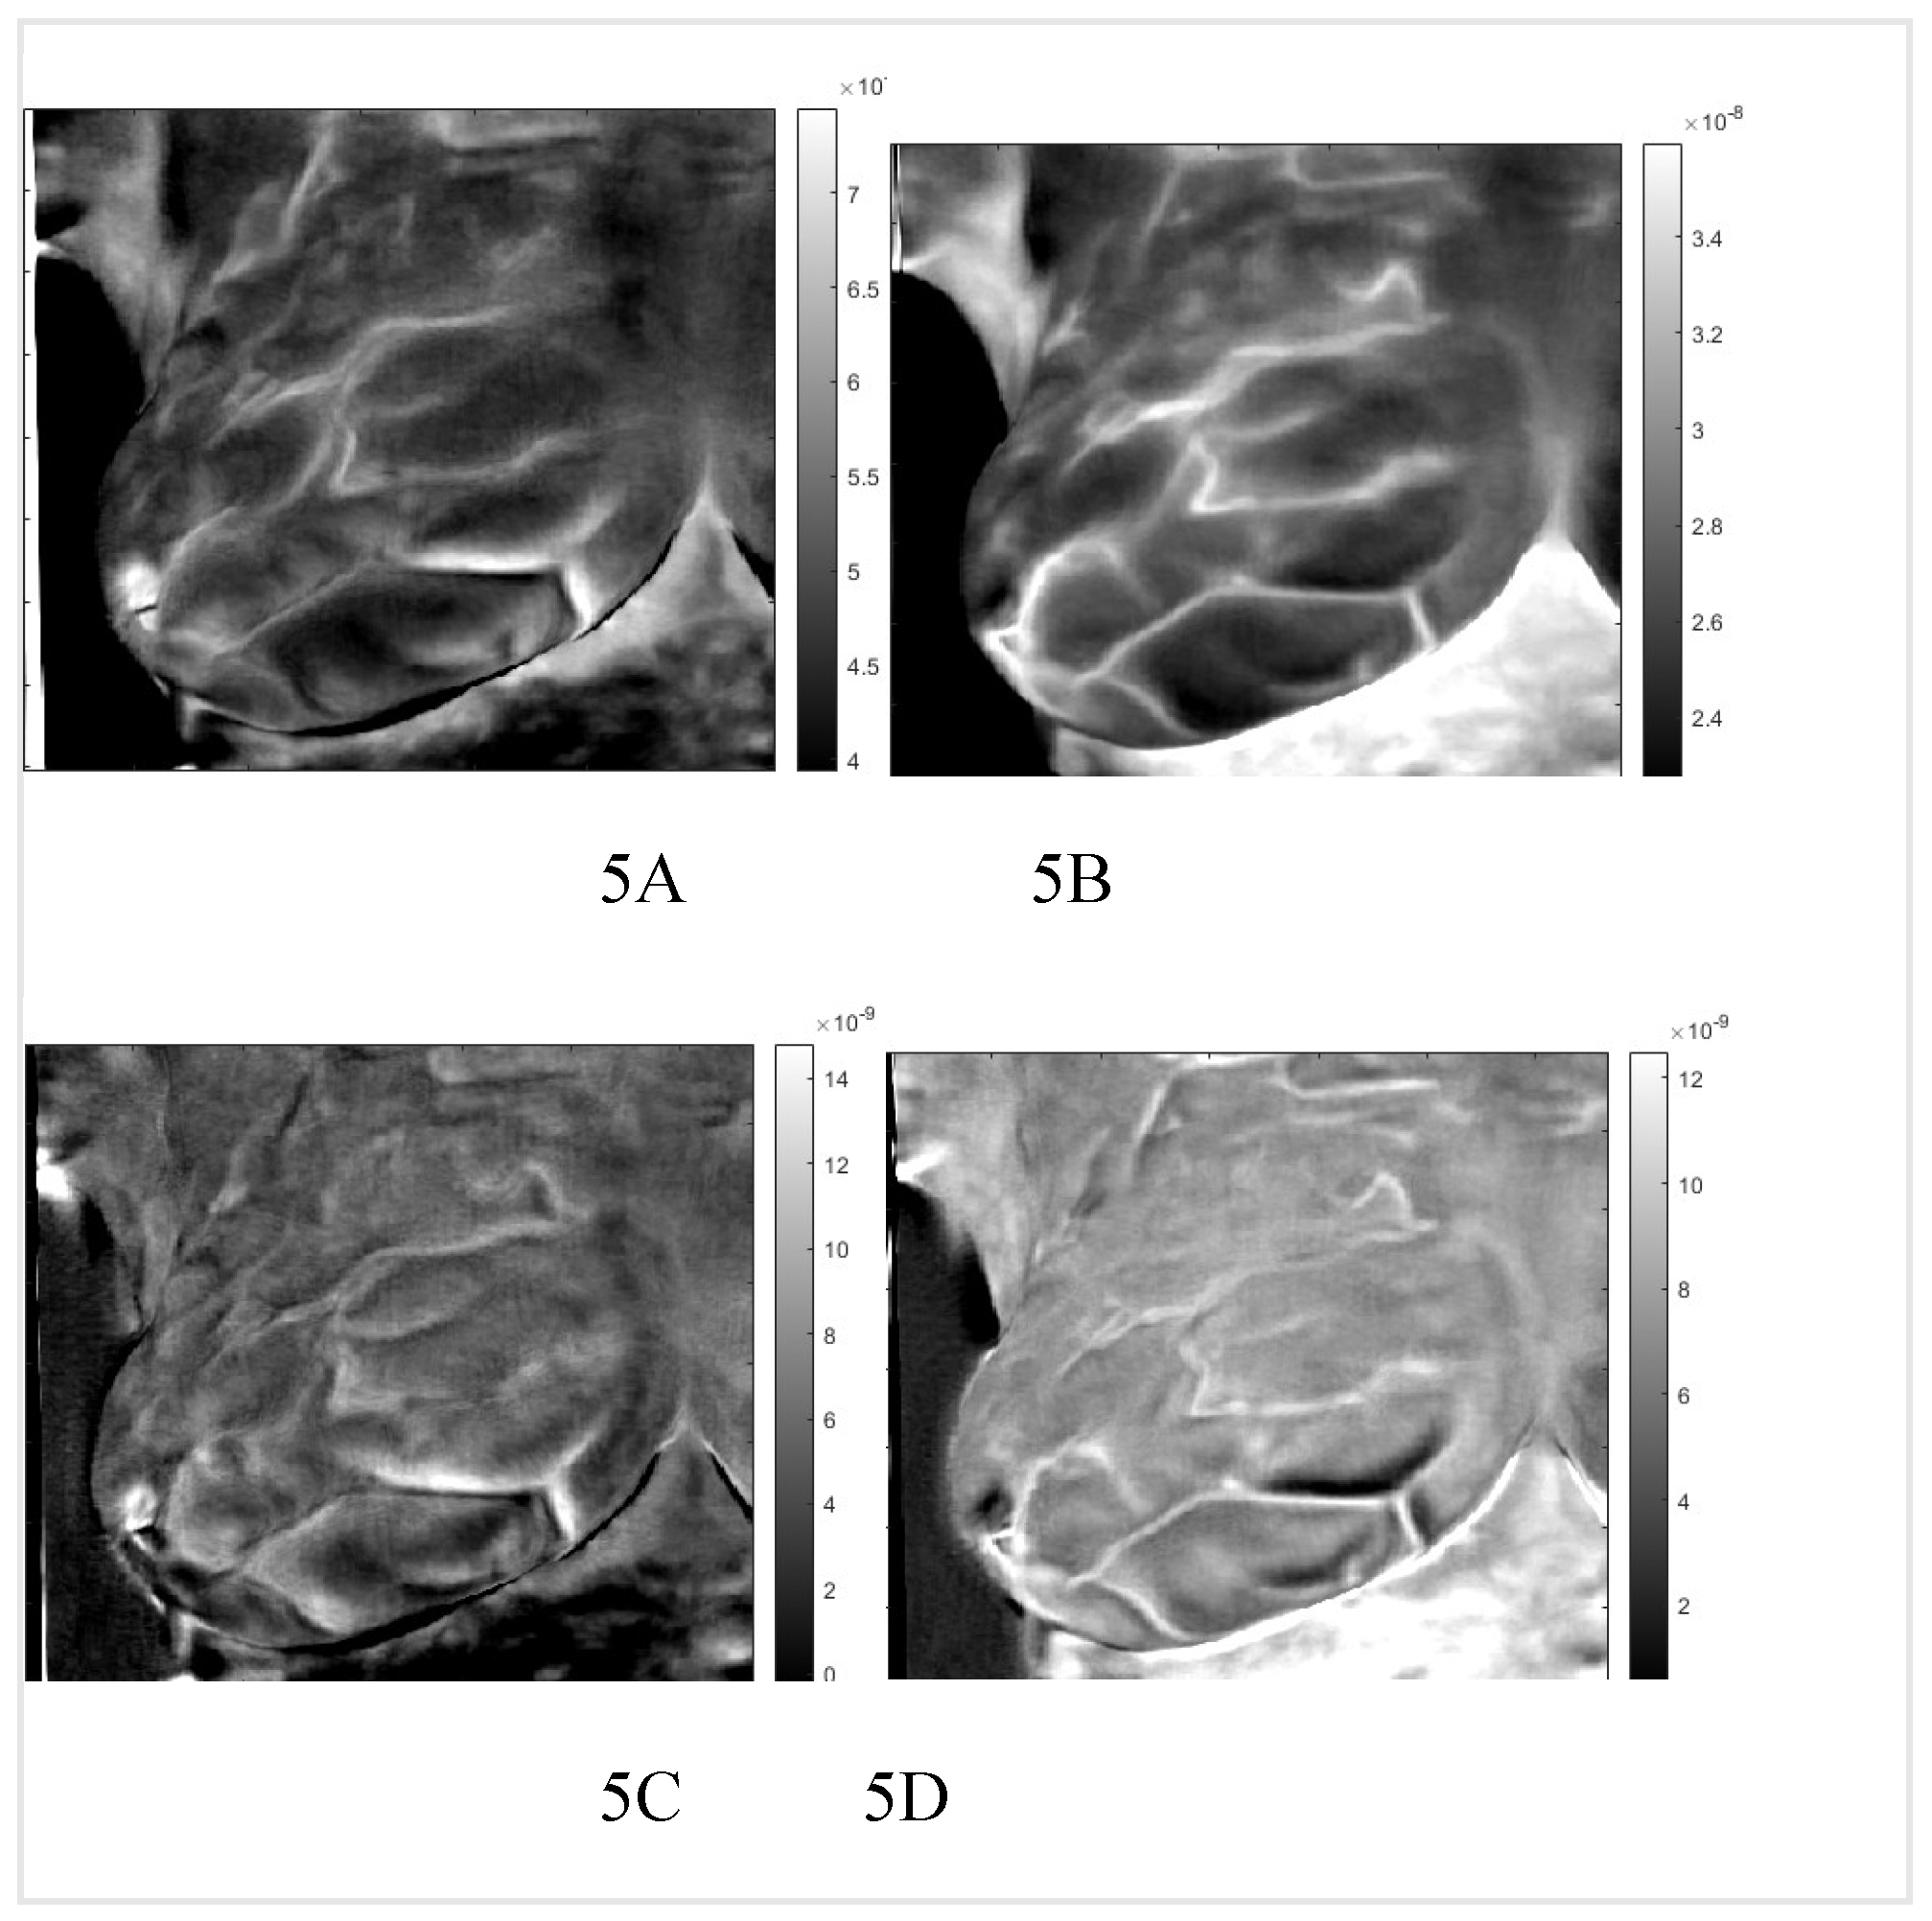

By applying the inverse transformation to the images 2-1 to 2-4, we get the images in Figure 5. In Figure 6, we present the result for the left breast, labeled "sick," and patient #T285 in Figures 7-1 to 7-4 for the left breast, labeled "healthy," and for the right breast, labeled "sick," in Figure 8. The supplemental material presents process images of patients #282 and #286.

Figure 5. Healthy right breast of patient “T281.” Images 1A: to 1D after application of the inverse PCI transform. A and B are images of thermal reflection, while C and D are images of vasoconstriction.

We identified two very similar thermal images at each breast. The first image is at the same polarity as the external cooling. The second image is from twice the depth of the first one and at the opposite polarity. Our interpretation is: The first reflection is due to vasoconstriction, while the second is due to thermal reflection. Skins nerves trigger vasoconstriction, which results in almost instantaneous constriction. The response to external cooling as a thermal regulation mechanism is the reduction of the heat conduct out of the vascular system, which is at the same polarity as the external cooling. The heat propagates only one way from the vascular system to the skin. Response by thermal reflection is different; the cooling traverses from the skin to the blood vessel, then reaches a constant temperature boundary, blood flow, and propagates back to the skin. The outcome is a signal with the reverse polarity of the cooling at twice the time of the first image. Figures six to eight show reflected heat in images one and three, while images two and four show vasoconstriction-generated signals. Comparing the images of the healthy and sick breast, we notice that the two images of reflection and vasoconstriction of the healthy breast are almost identical; on the other hand, in the sick breast, we can see a difference: Some of the vessels in the vasoconstricted images are not visible or are at reduced intensity; they barely constrict in comparison to a healthy one. We noticed similar behavior in the supplemental images. This reduced constriction might be highly significant as it could be helpful in cancer screening. Remember that the data set had only four image sequences identifying the sick breast.